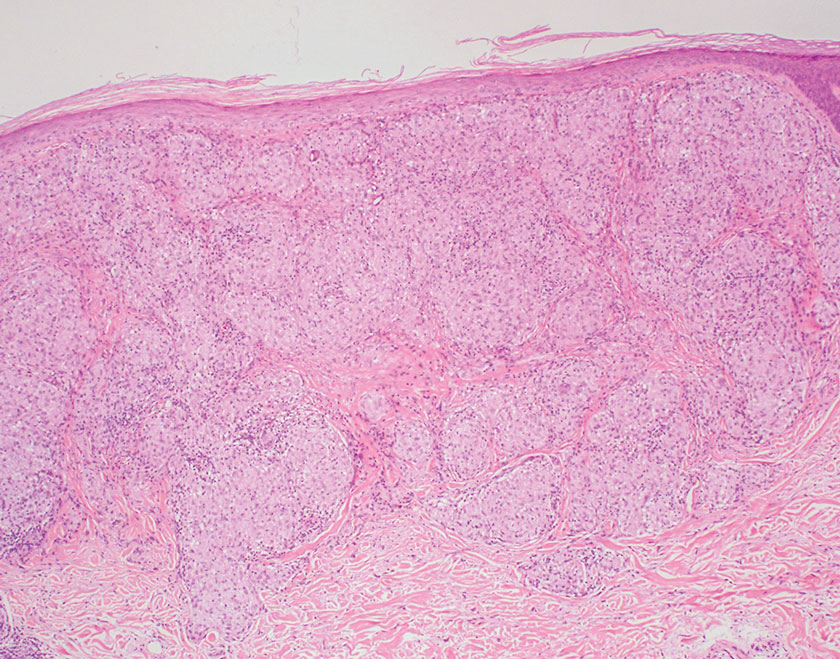

Histopathology showed collections of epithelioid to sarcoidal granulomas throughout the dermis and clustered around nerve bundles with a grenz zone at the dermoepidermal junction. Fite stain was positive for acid-fast bacteria, which were confirmed to be Mycobacterium leprae by by the National Hansen’s Disease program. Based on these findings, a diagnosis of lepromatous leprosy (LL) was made. The patient was treated by the infectious disease department with multidrug therapy that included monthly rifampin, moxifloxacin, and minocycline; weekly methotrexate with daily folic acid; and an extended prednisone taper with prophylactic cholecalciferol.

Lepromatous leprosy transmission is not fully understood but is thought to occur via airborne droplets from coughing/sneezing and nasal secretions.2 Histopathology generally shows a dense and diffuse granulomatous infiltrate that involves the dermis but is separated from the epidermis by a zone of collagen (grenz zone).3 Histology is characterized by the presence of lymphocytes and numerous foamy macrophages (lepra or Virchow cells) containing M leprae organisms. In persistent lesions, the high density of uncleared bacilli forms spherical cytoplasmic clumps known as globi within enlarged foamy histiocytes (Figure 1).4 The macrophages form granulomatous lesions in the skin and around nerve bundles, resulting in tissue damage and decreased sensation. The current standard of care for LL is a multidrug combination of dapsone, rifampin, and clofazimine. Early diagnosis and complete treatment of LL is crucial, as this approach typically leads to complete cure of the disease.